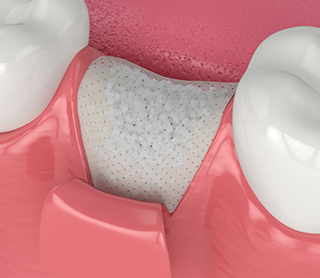

骨再生誘導法GBR(Guided Bone Regeneration)

インプラント治療などで骨の厚みや高さが不足している部分に、メンブレンという人工膜を設置し、歯肉の侵入を防ぎながら骨の再生を促す治療法です。骨がしっかり再生されることで、インプラントの安定した埋入や長期的な維持が可能となり、審美性・機能性の高い治療結果につながります。